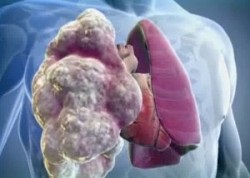

Ebben a kórtanában az alveolák erősen kibontakoznak, ami a tüdőszövetet túlságosan szellősvé teszi, és az alveolusok falai is elkezdenek lebomlani. A betegség leggyakrabban az erősebb szex képviselőiből szenved - közel kétszer annyi, mint a nőknél. Veszélyeztetettek az 55 és 60 év közötti emberek krónikus tüdőbetegségekkel.

Amikor a tüdőbetegség élei különböző légköri buborékokkal töltődnek fel. Méreteik 1 és 10 cm között változhatnak, a bolla egyszersmind vagy tömeges klaszterekből állhat. A betegségnek ez a formája van: a beteg gyorsan kialakul légzési elégtelenség. És ennek oka nemcsak a tüdőtágulat, hanem az egészséges tüdőszövet összeszorítása is. Ennek eredményeképpen a helyszín létfontosságú aktivitása és működése, melyet a bullae szaggatott, súlyosan megzavarodott. A bullous emfizéma következményei sokkal veszélyesebbek és súlyosabbak, mint a közös patológia következményei.